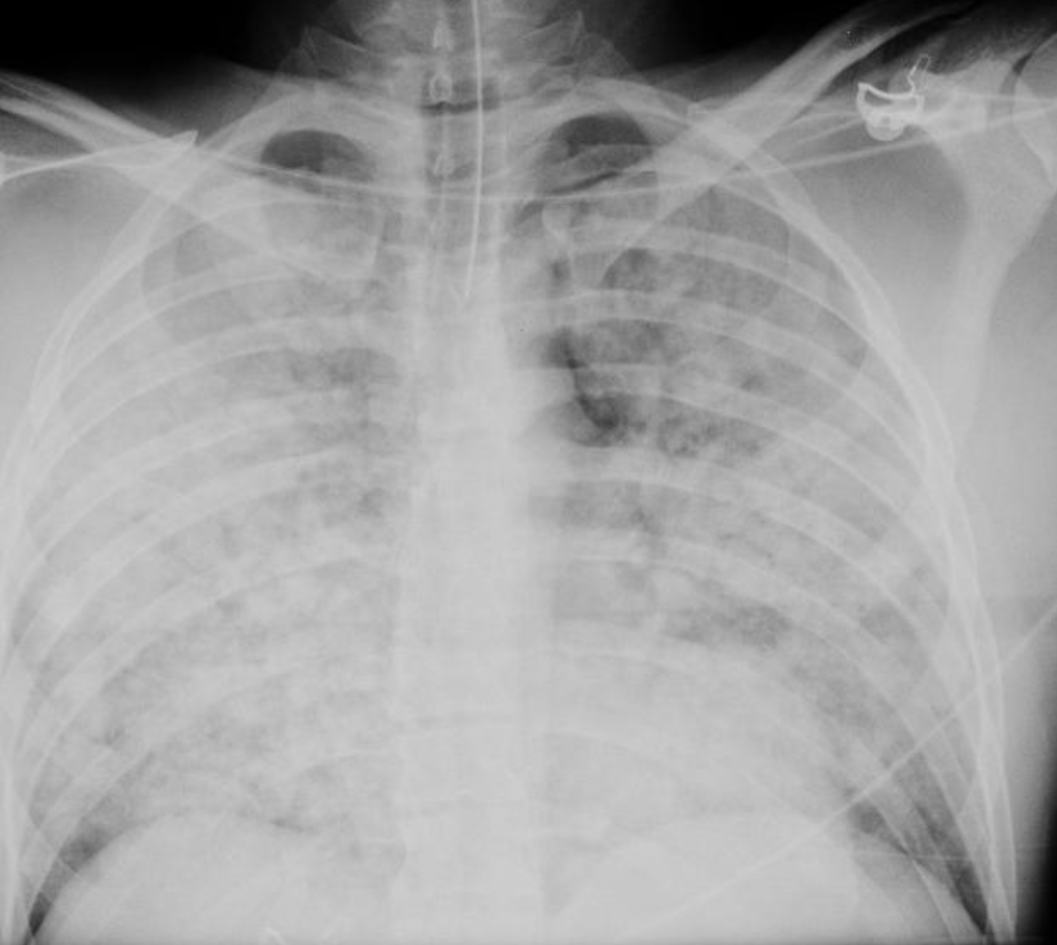

Identify this radiograph.

What are cannonball lesions or metastatic disease?

Name this critical imaging finding.

What is near drowning?